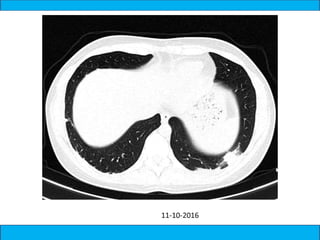

A medical document discusses hypoxia following a road traffic accident. It describes four types of pulmonary contusion caused by direct chest compression, shearing against vertebral bodies, fractured ribs directly injuring the lung, or tearing of lung parenchyma due to prior adhesions. The document also mentions management of pulmonary contusion.